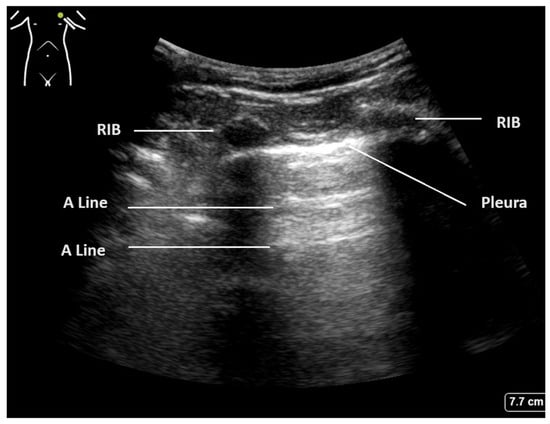

| Normal aerated lung | Movement of the pleural line with tidal ventilation Presence of A-lines (Figure 1) Maximum of 2 B-lines per image |